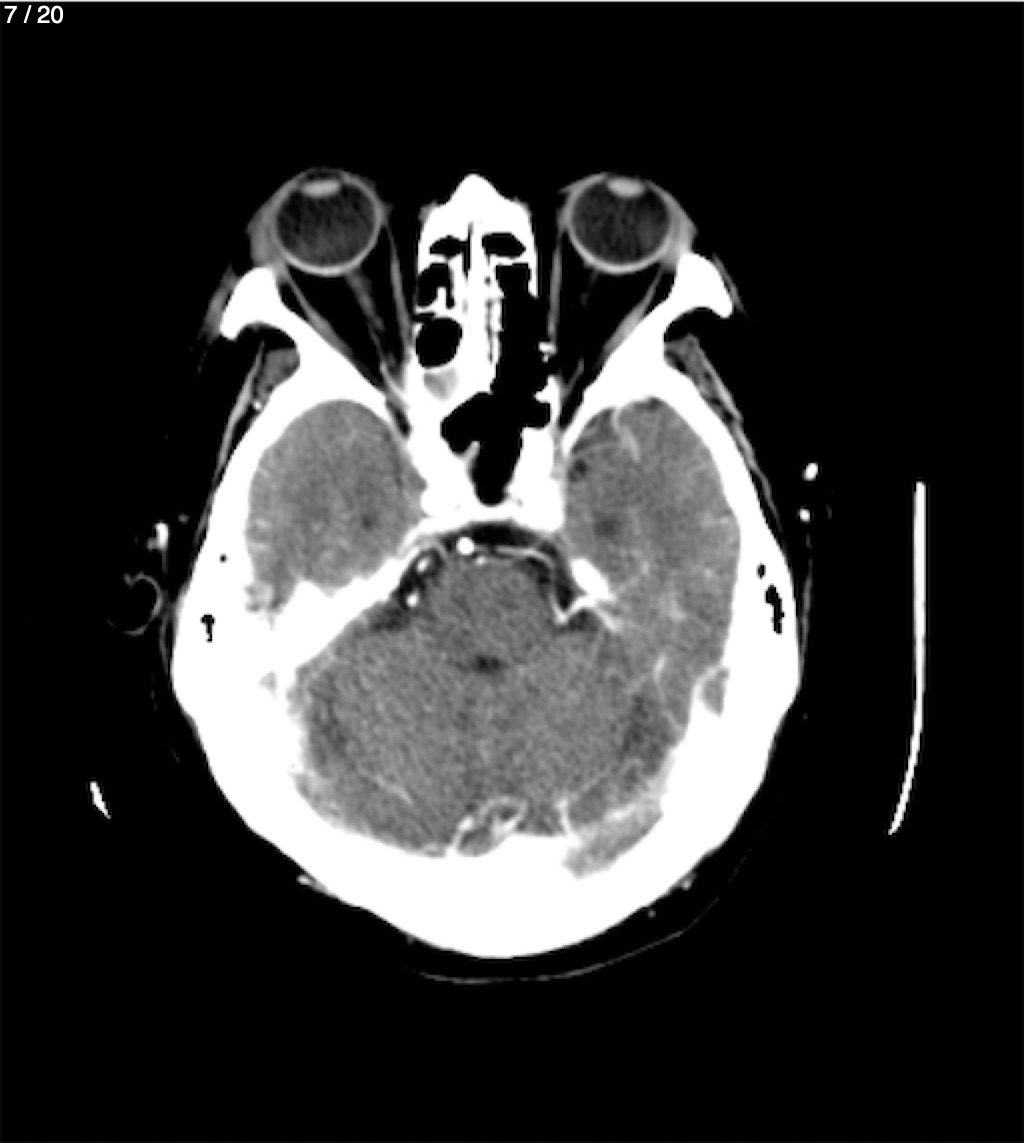

Jose Sosa Martinez 66A - Angiotac Craneo